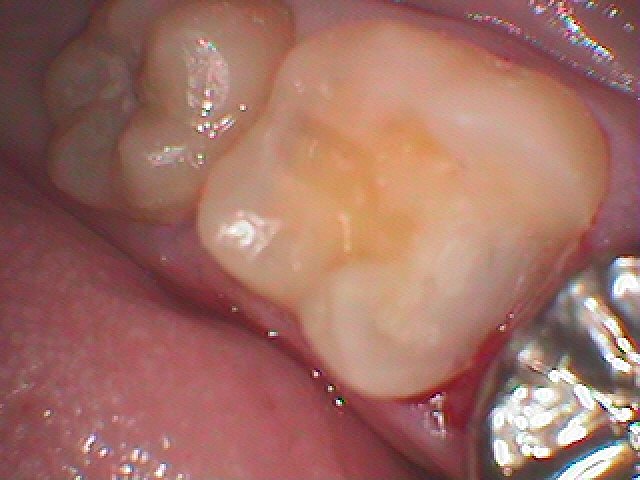

神経に気を付けながら虫歯を除去していきました

CR樹脂にて覆罩を行っています